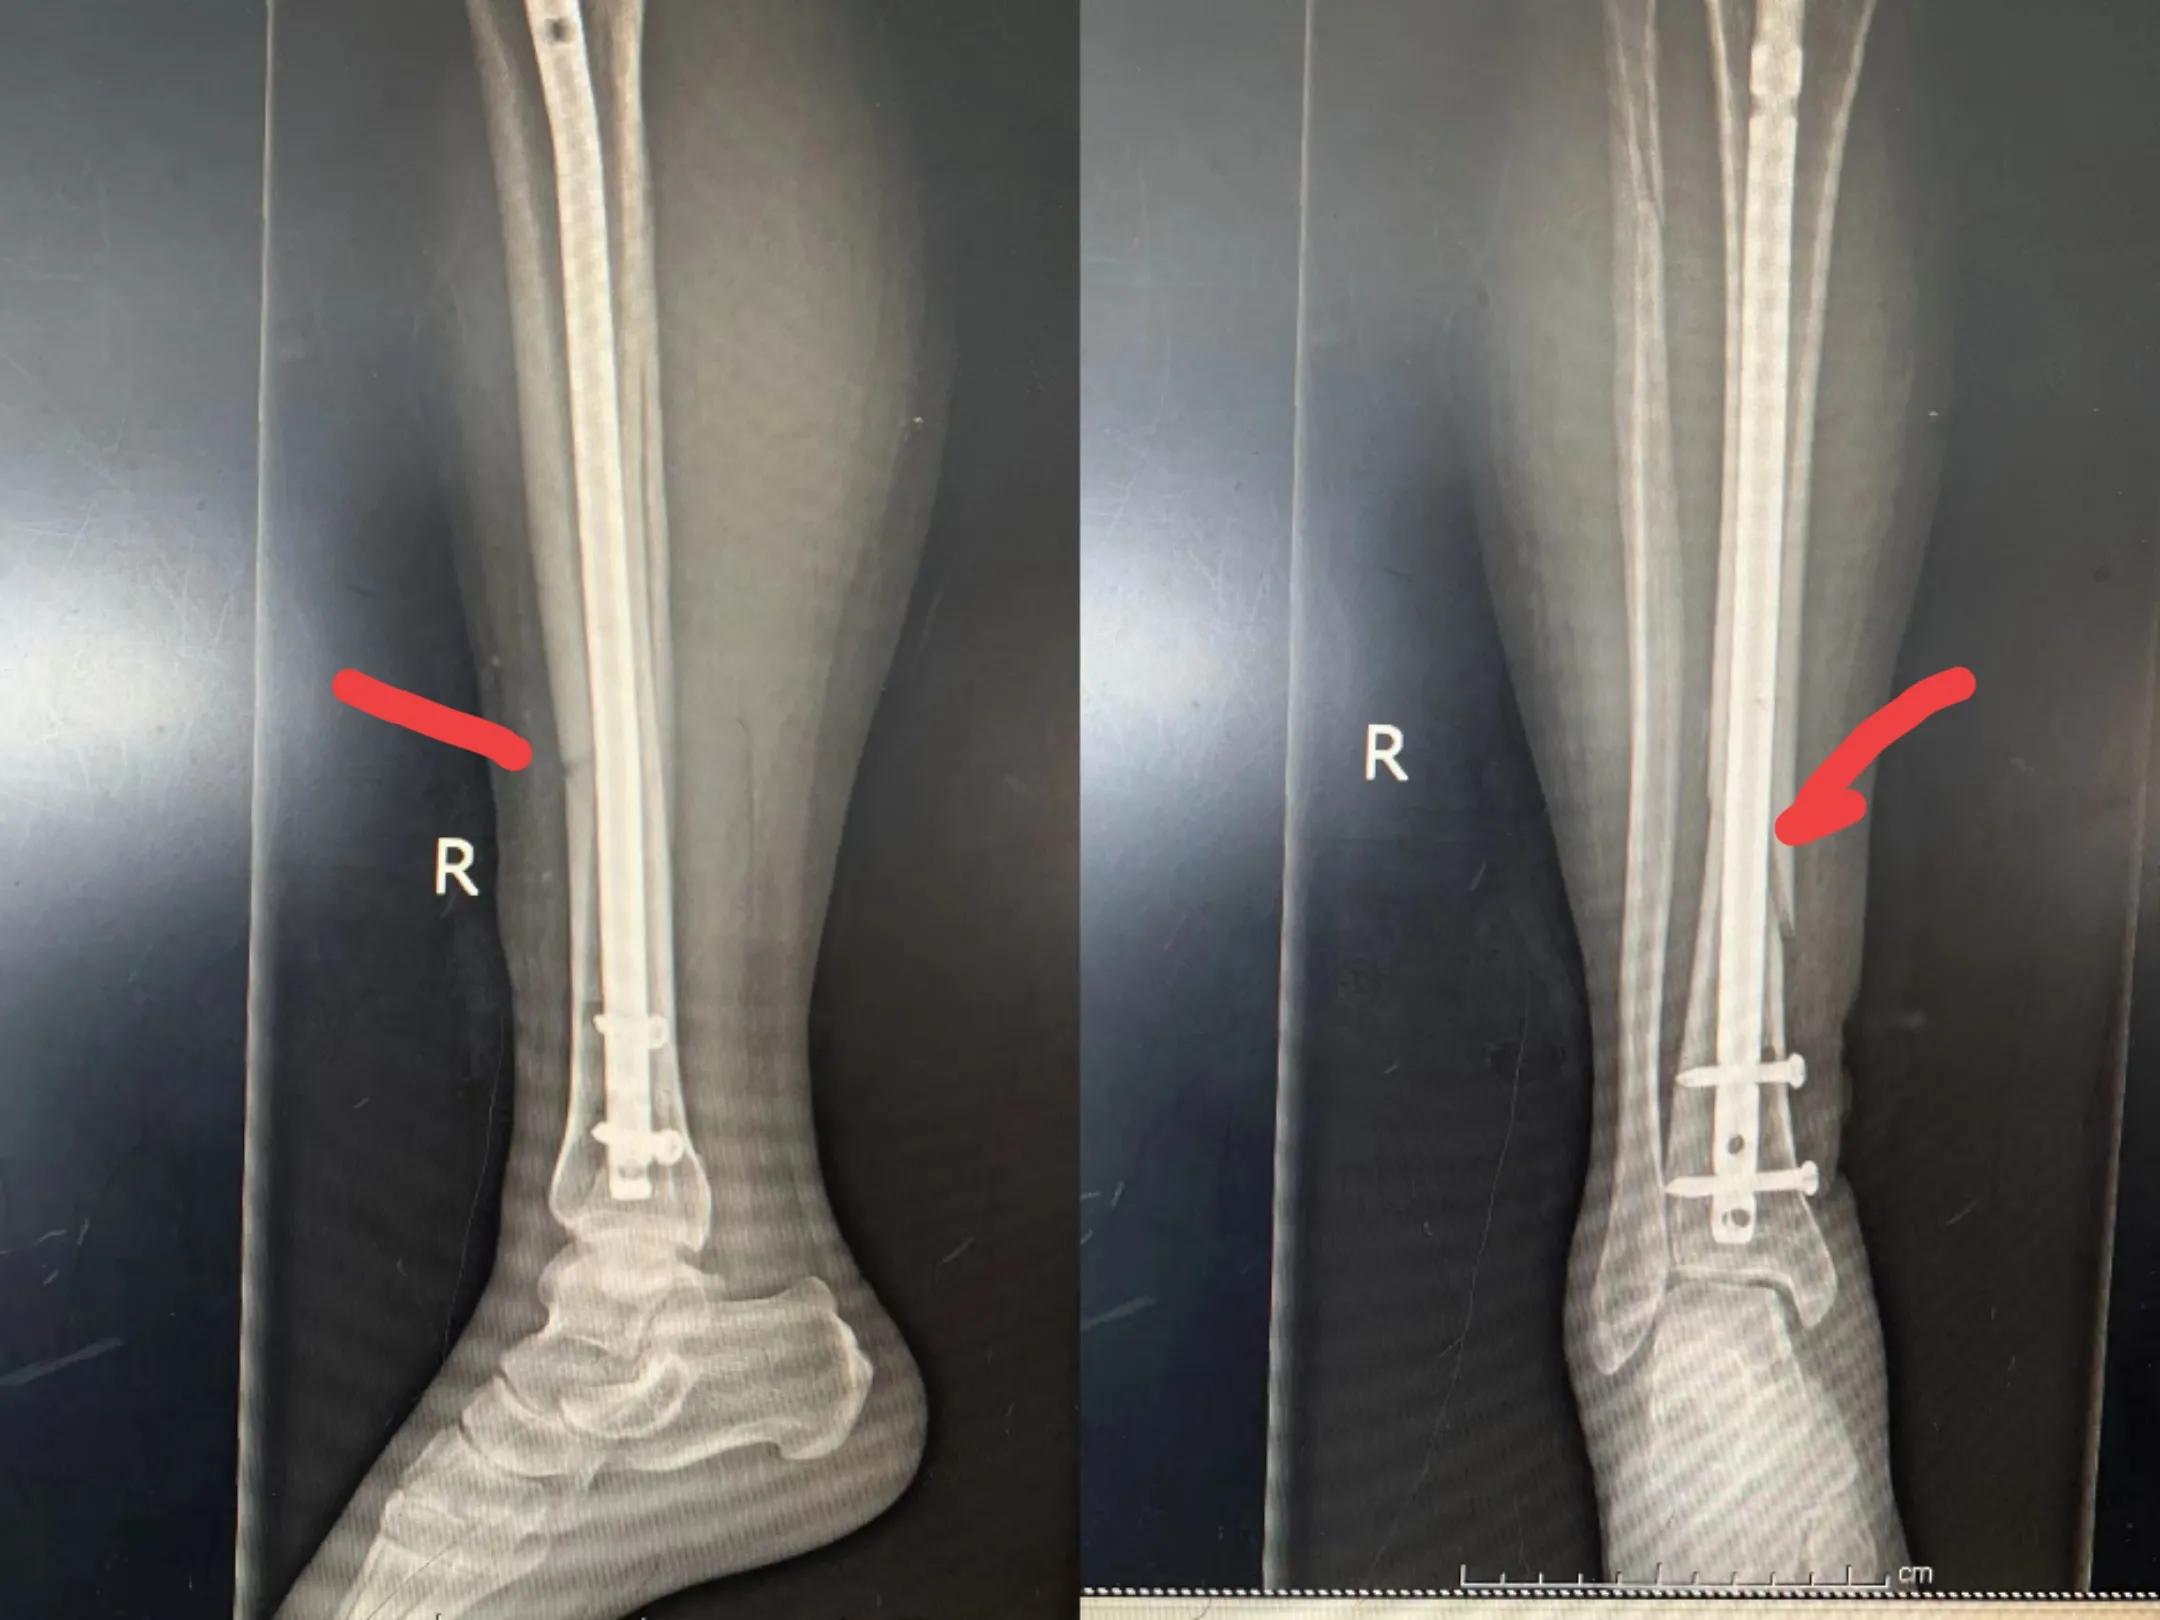

胫骨骨折包括胫骨平台骨折、胫骨干骨折和胫骨远端骨折,是骨科常见的骨折类型,多数合并有腓骨骨折。可见于任何年龄段人群。

手术治疗内固定物包括钢板,髓内钉,螺钉,外固定架等。